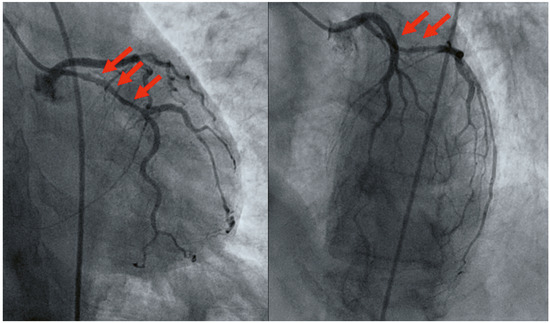

Notre premier cas clinique est celui d’une femme de 39 ans sans comorbidités ou FRCV qui a accouché par voie basse sans complications une semaine auparavant (3ème accouchement). Elle est adressée aux urgences pour des douleurs thoraciques oppressives d’apparition brutale au repos avec une irradiation dans l’épaule gauche et associées à une dyspnée. L’ECG d’entrée montre des troubles de la repolarisation compatibles avec un STEMI inférieur. La coronarographie montre une lésion significative de l’artère circonflexe proximale qui s’étend jusqu’à une sténose significative de la première marginale et une sténose significative du segment distale de l’artère circonflexe (Figure 1). Les images parlent en faveur d’une SCAD de type 2A. Nous décidons d’un traitement conservateur et la patiente est hospitalisée pour surveillance. Le bilan biologique montre une élévation des enzymes cardiaques avec des troponines élevées (13 481 ng/l, norme 4–16 ng/ l ) et des CK élevées (6114 U/l, norme 25–190 U/l). Une échographie cardiaque a mis en évidence une FEVG estimée à 48% avec une akinésie inférolatérale. Le traitement par aspirine 100 mg et métoprolol 37,5 mg est débuté. Pendant la surveillance, la patiente reste hémodynamiquement stable sans troubles rythmiques ni récidive des douleurs thoraciques. Ce cas est l’illustration d’une SCAD sans argument pour une vasculopathie sous-jacente.

Figure 1.

Sténose tubulaire avec HIM de l’artère coronaire circonflexe proximale (SCAD type 2A).